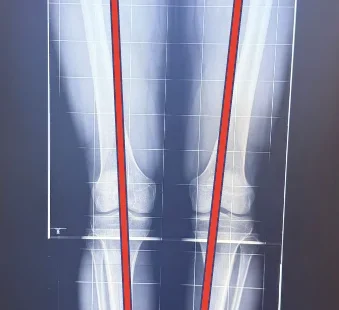

HTO is a procedure to correct the leg alignment by making a planned bone cut on the tibia. The goal is to shift the load from the damaged area to the healthier area, thereby reducing pain and functional problems.

Associated with varus (bow-leg) deformity